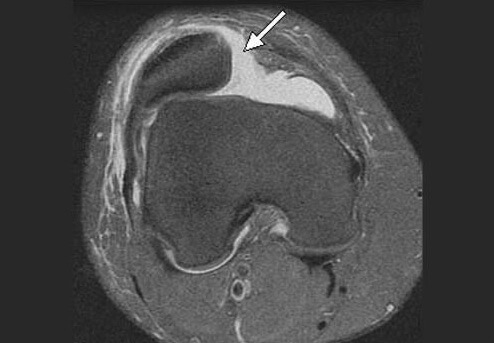

Вивих надколінка – одна з частих травм колінного суглоба. В нормі, надколінок фіксується та утримується чотириголовим м’язом стегна, власною зв’язкою надколінка та двома зв’язками-утримувачами (медіальна зовнішня підтримуюча зв’язка надколінка та латеральна-внутрішня підтримуюча зв’язка